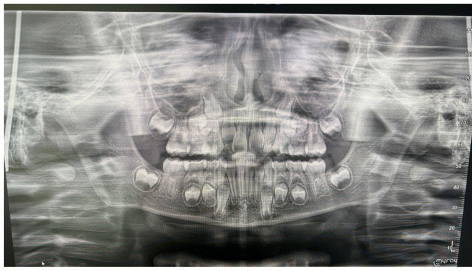

The patient was a young female presenting with a Class III dento-skeletal malocclusion, which was treated using the AMCOP® TC appliance. A comprehensive diagnostic protocol was carried out both before and after treatment, including orthopantomography (Figure 2–3), postero-anterior teleradiography (Figures 4, 5), latero-lateral cephalometric radiography (Figures 6, 7), cephalometric analysis (Tables 1, 2), as well as extraoral (Figures 8, 9) and intraoral photographs (Figures 10, 11). The extraoral examination revealed an edge-to-edge incisal relationship and the presence of a midline diastema. Pre-treatment cephalometric analysis (Deltadent® Lana, Bolzano, Italy) confirmed the diagnosis of a skeletal Class III malocclusion. The treatment plan involved the use of the AMCOP® TC appliance. The patient was instructed to wear the device for two hours in the afternoon and throughout the night for the first six months, followed by nighttime use only for an additional six months. Upon completion of the treatment, the patient achieved a Class I occlusion, with correction of both overjet and overbite. Additionally, the device facilitated tongue re-education and contributed to the postural realignment of the first cervical vertebra.